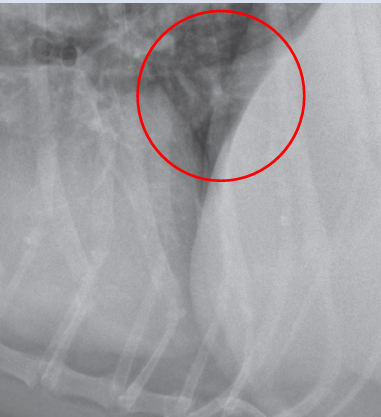

arrow pointed the THYMUS

dark white: right margin of trachea

light white arrow: left margin of trachea

Lymphomegaly

Heart base mass